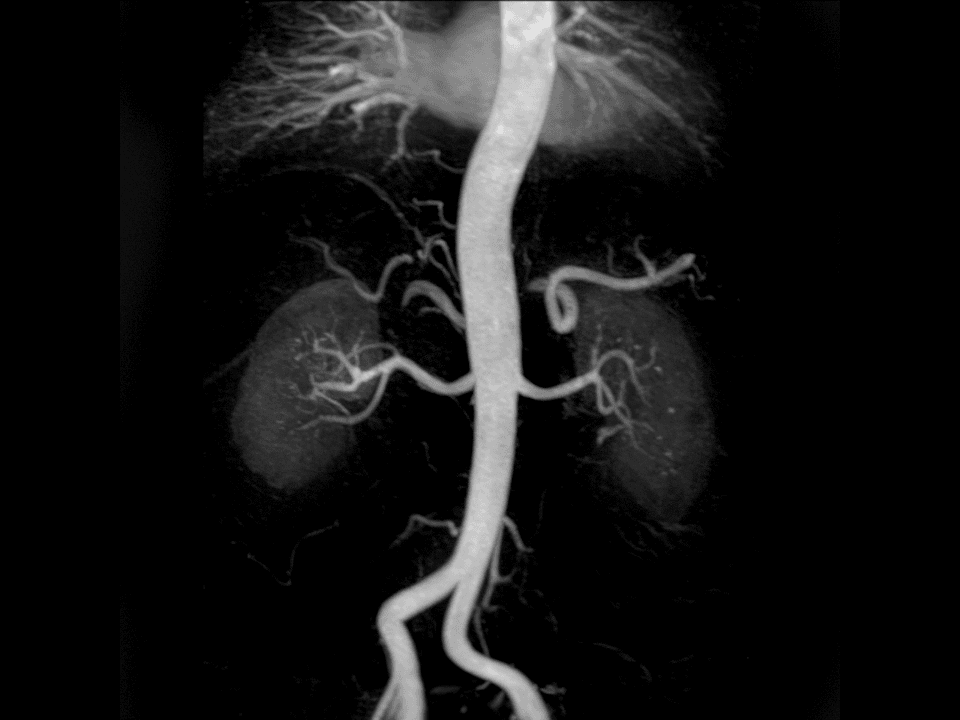

Easily depict vessel diseases with contrast and non-contrast enhanced techniques.